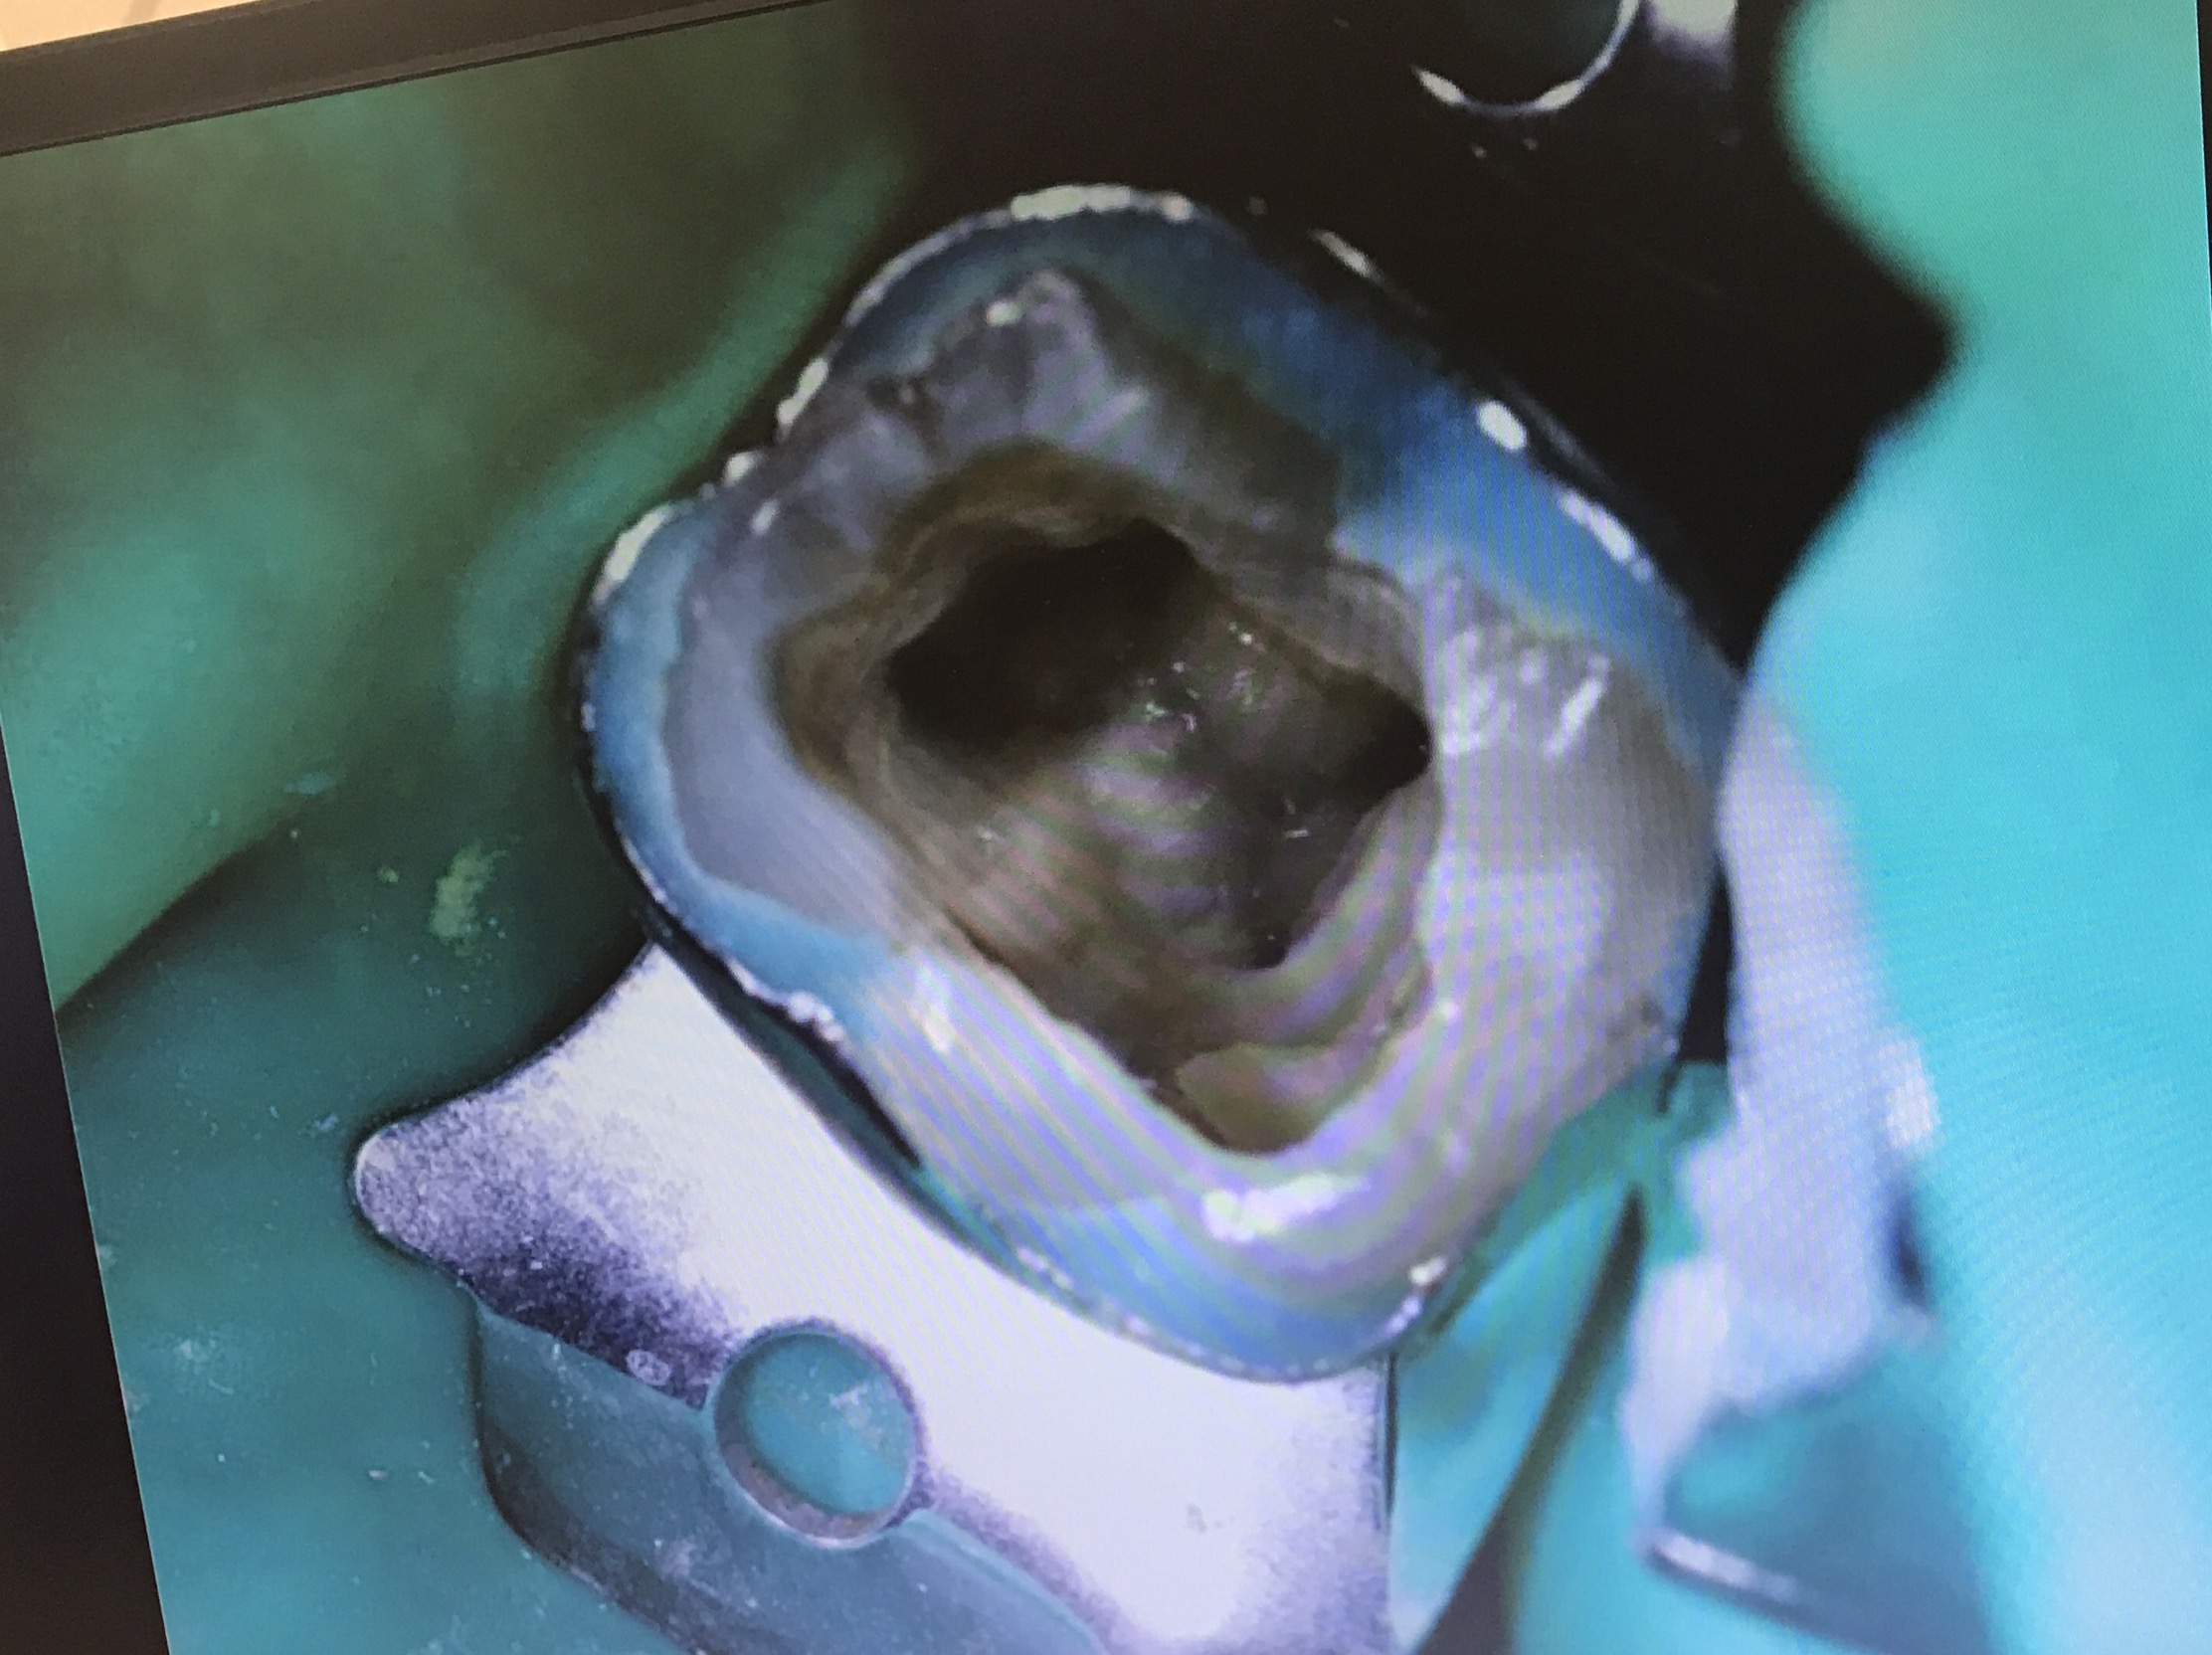

อันนี้คือ case จริงครับ ส่วนที่ Outline ไว้ตรงกลางคือ รอย Perforate

repair ใช้ MTA และ wet cotton (เพื่อให้ set)